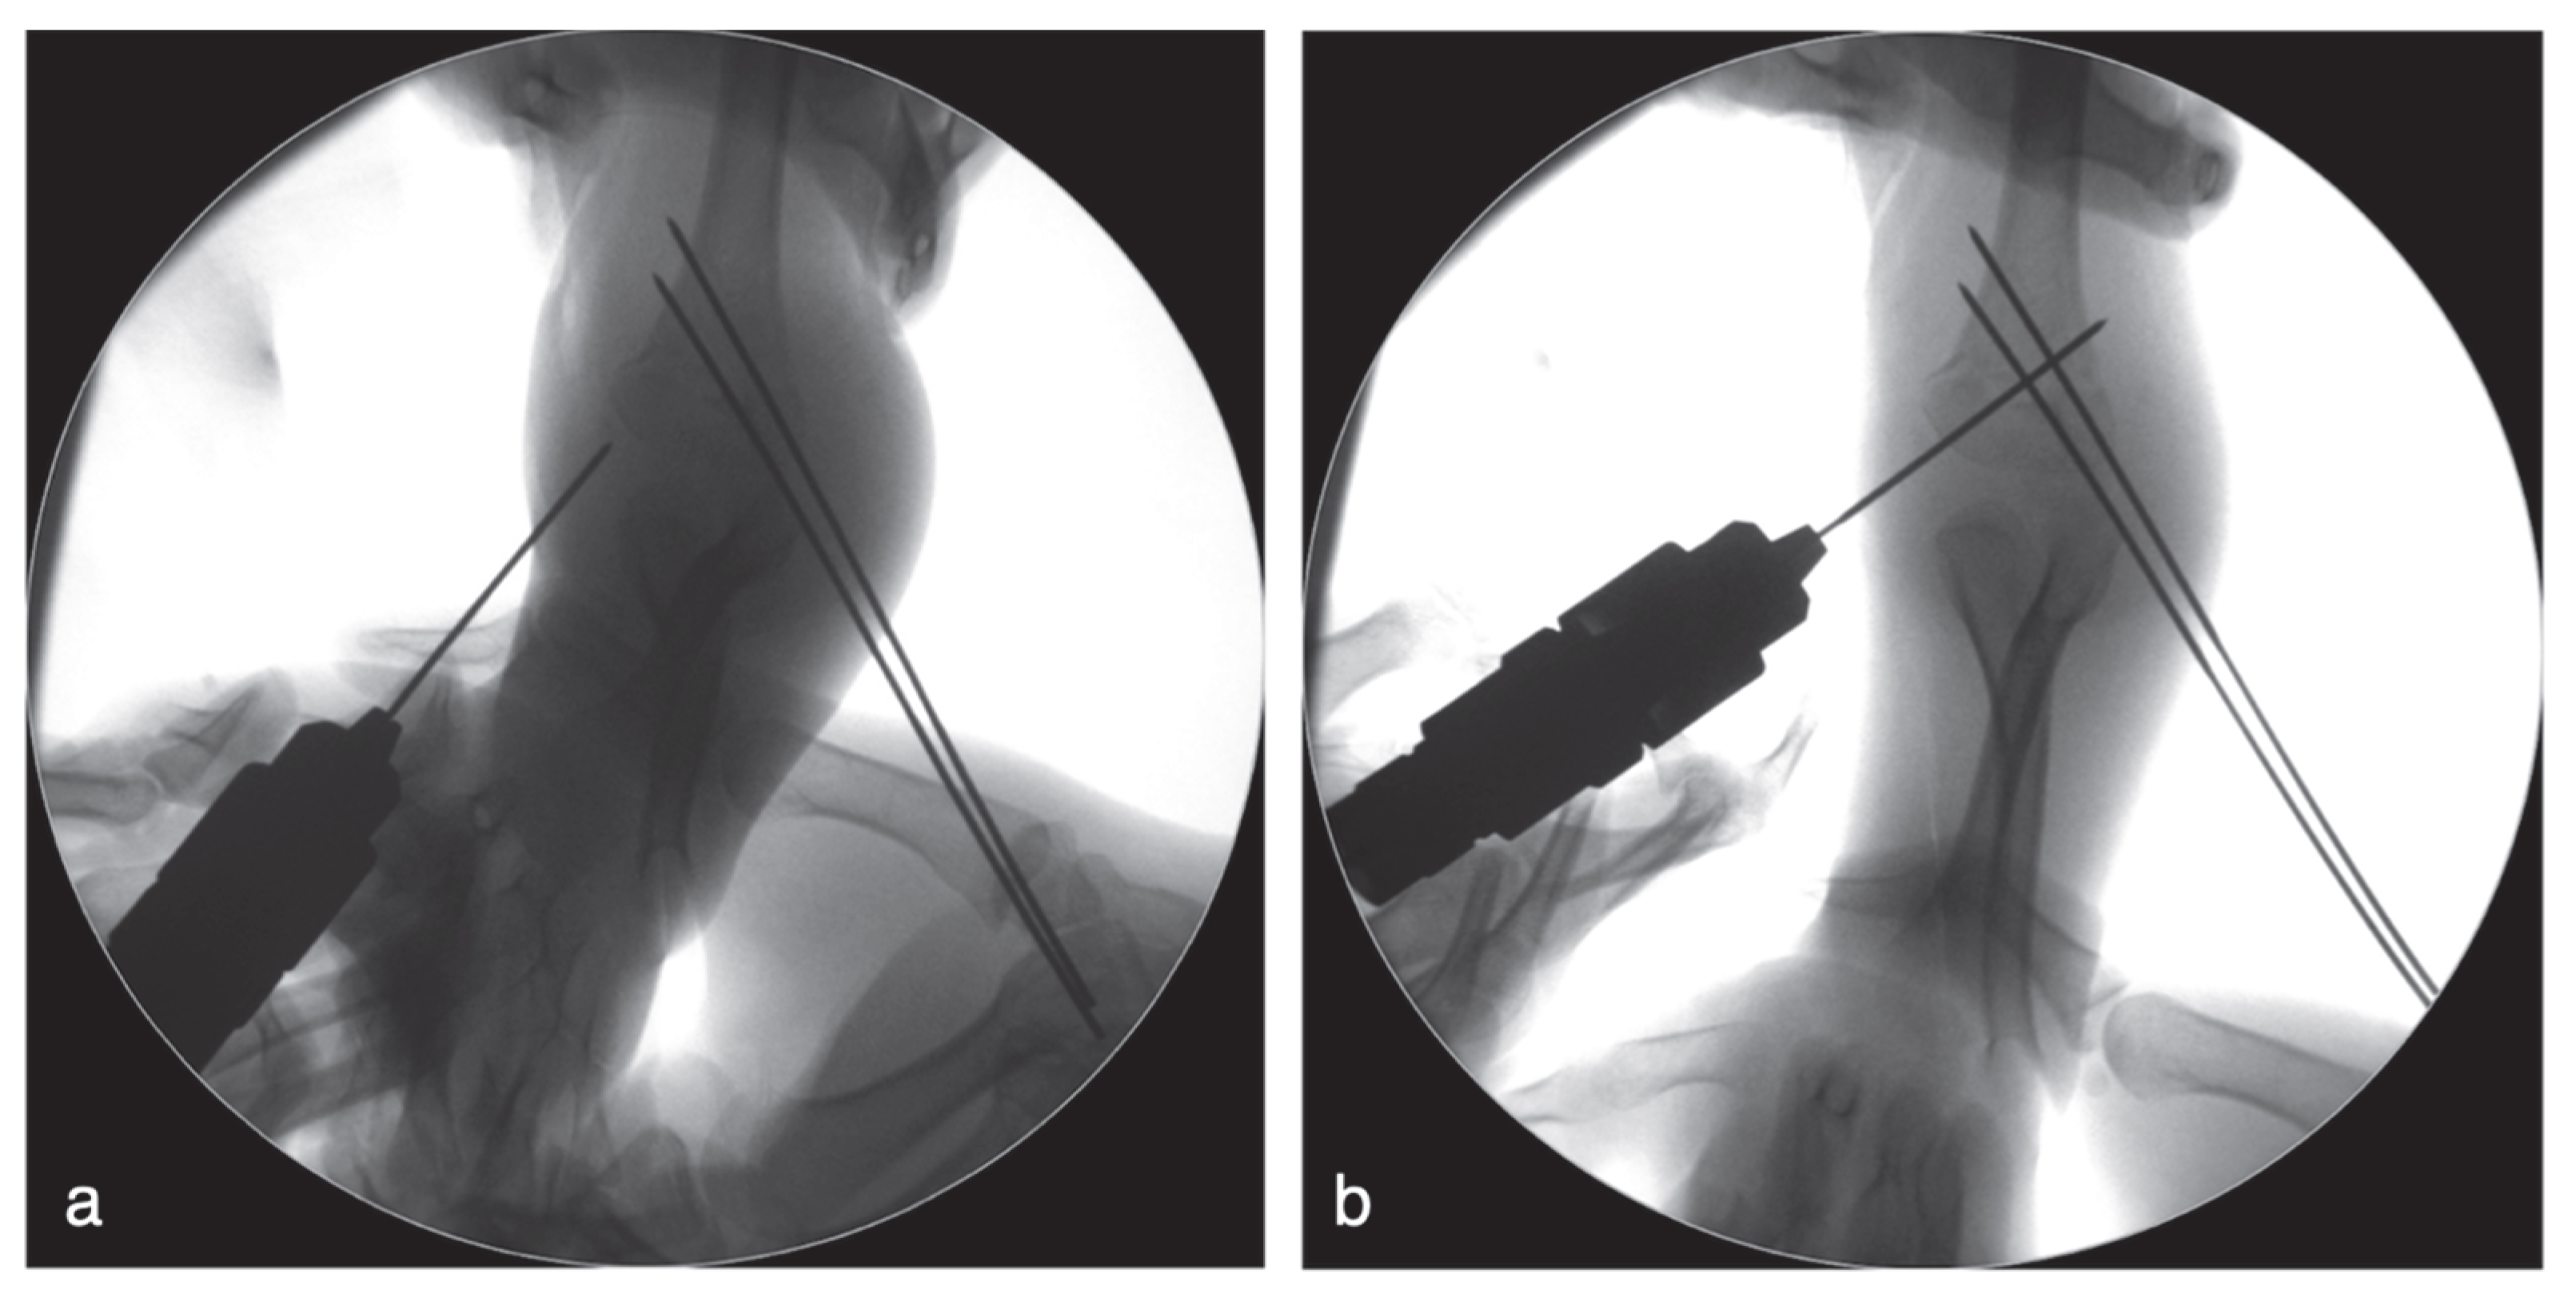

The injured arm was disinfected and draped in a standard sterile manner. Reduction began under anteroposterior (AP) fluoroscopic view. Coronal translation and rotation of the distal fragment were corrected under AP view, after which the view was switched to lateral fluoroscopy to restore sagittal alignment. Sagittal reduction was performed using the joystick method: the surgeon inserted the blunt end of a Kirschner wire (K-wire) into the fracture site and used it as a lever to correct sagittal-plane malalignment (

Figure 2).

If reduction was unsatisfactory, the surgeon made fine adjustments by applying gentle thumb pressure over the distal fragment. Once acceptable reduction was achieved, fixation was performed using a configuration of two lateral pins and one medial pin. A K-wire was inserted diagonally from the lateral condyle, through the fracture, to engage the medial supracondylar ridge. A second lateral-entry pin was then inserted more medially on the lateral condyle, either divergent from or parallel to the first pin, to further stabilize the fracture (

Figure 3a). After inserting the two lateral K-wires, we assessed fixation stability by flexing, extending, and rotating the elbow. If instability was observed (for example, relative displacement or angular change under C-arm fluoroscopy), we proceeded to place a medial pin. The elbow was then held in approximately 60° flexion. Because the lateral pins stabilized the fragments, mild extension maintained alignment and relaxed the ulnar nerve, reducing the risk of anterior subluxation (